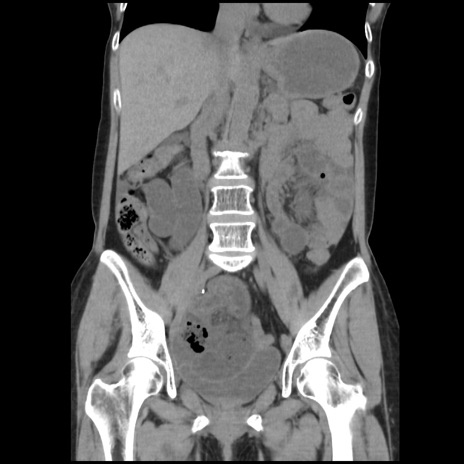

横断像